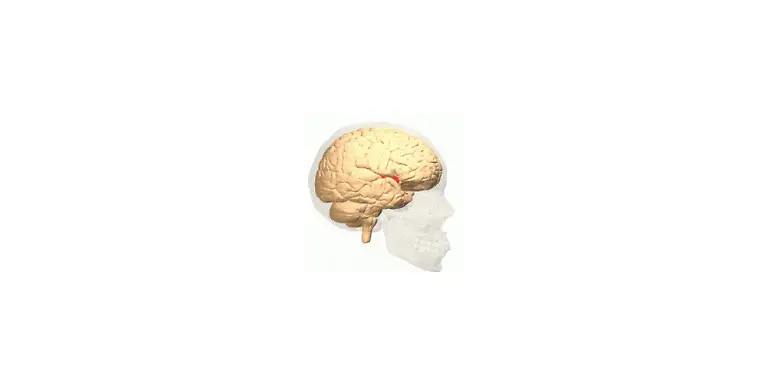

Egal, ob es ums Sehen oder Hören geht, ums Atmen, Sprechen, Rechnen oder Laufen: Stets sind es Milliarden grauer Zellen, die diese Fähigkeiten ermöglichen. Viele verschiedene Bereiche des Gehirns arbeiten zusammen, um die unterschiedlichsten Aufgaben zu lösen. Was wird von wo gesteuert? n-tv.de erklärt, was es mit Frontallappen, Mandelkern & Co. auf sich hat.